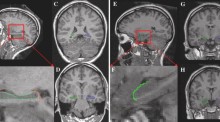

Tracing superior longitudinal fasciculus connectivity in the human brain using high resolution diffusion tensor tractography Arash KamaliAdam E. FlandersKhader M. Hasan Original Article 04 January 2013 Pages: 269 - 281